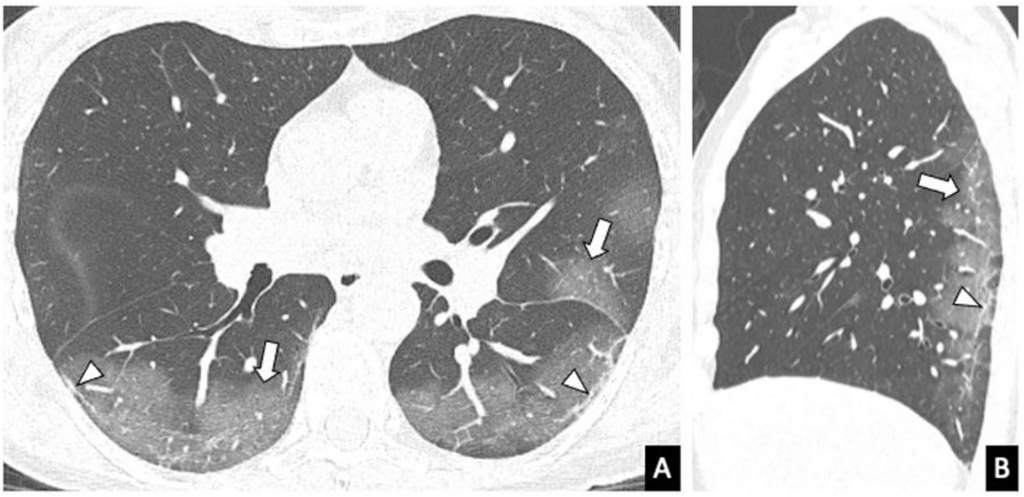

El Dr. Sebastián Fernández-Bussy, autor principal del estudio, destacó que muchas de las anomalías detectadas en tomografías de tórax son benignas, pero algunas son peligrosas. La tecnología robótica permite diferenciarlas con rapidez y precisión, reduciendo complicaciones y aumentando la eficacia del tratamiento.

El estudio se centra en la broncoscopia asistida por robot con detección de forma, autorizada por la FDA en 2019. Esta técnica permite:

El análisis incluyó 2.115 lesiones pulmonares en 1.904 pacientes en centros Mayo en Florida, Arizona y Minnesota. Los resultados muestran un cambio significativo: